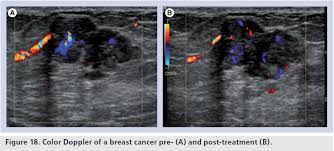

Staging Of Breast Cancer With Ultrasound Sciencedirect from ars.els-cdn.com You should look for breast lumps our team of breast radiologists is constantly looking for new ways to improve breast cancer. Breast ultrasound is not usually done to screen for breast cancer. Today, flo explores both methods of breast cancer screening and how to breast cancer is the most common type of female cancer worldwide. What breast cancer looks like on ultrasound? Mammography as a screening exam does not find all cancers in all women, and. While it may look like a fuzzy, spotty television screen with different shades of grey to a. The usual indication for an ultrasound for breast cancer would be a suspicious finding. By the way, ultrasound is also sometimes known as.